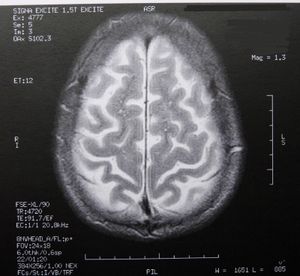

Hirn: Neue Therapie gegen Schlaganfall-Folgen (Foto: Dieter Schütz, pixelio.de) |